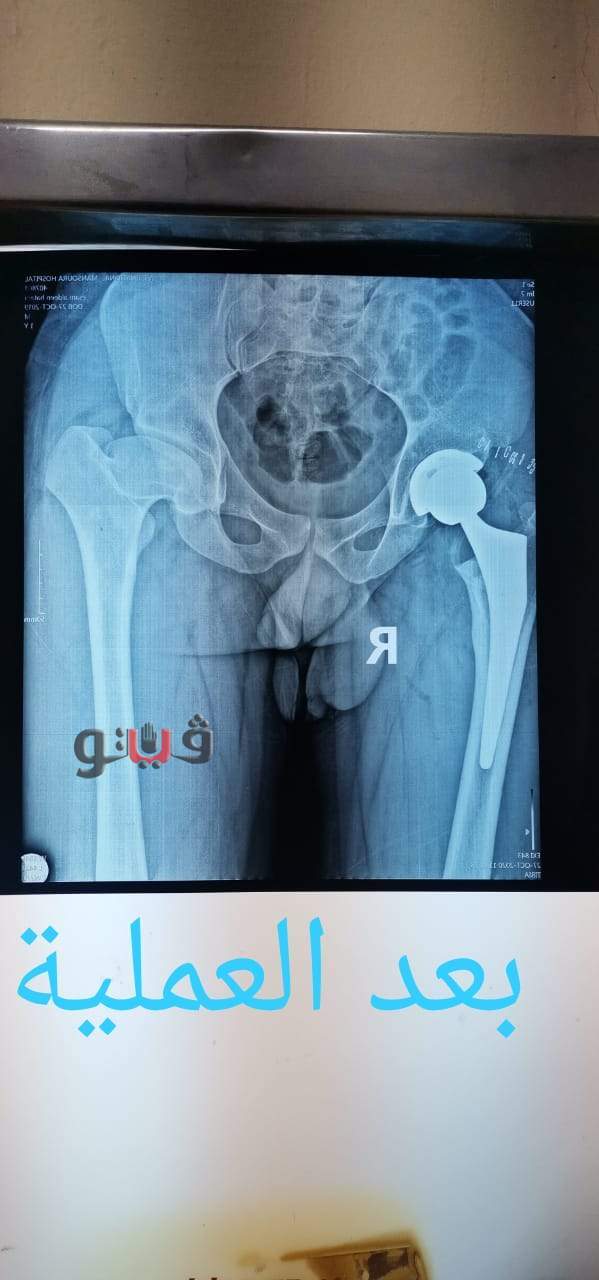

استغرقت 3 ساعات .. استبدال مفصل الفخذ بآخر صناعي لمريض بالمنصورة

شهد مستشفي بمستشفى المنصورة العام الجديد الدولي سابقا قيام فريق طبي، بإجراء جراحة دقيقة وحرجة لمريض يبلغ من العمر 22 عاما كان يعاني من تآكل في مفصل الفخذ مع تشوه بمفصل الحق وكان ضمن الحالات الحرجة لقوائم الانتظار.

وتمكن الفريق الطبي من إجراء استبدال كامل لمفصل الفخذ بمفصل صناعي غير أسمنتي وتم استعادة طول العظمة، واستغرقت العملية حوالي ثلاث ساعات وتعد هذه العملية من الجراحات المتقدمة ذات المهارة الخاصة.